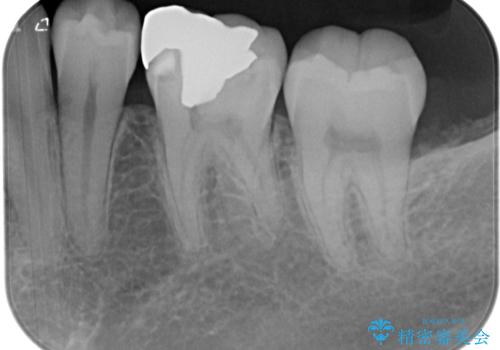

- 左下の銀歯のところがしみるとのことで来院された患者様です。

レントゲン上で金属の詰め物(メタルインレー)の下に虫歯を認めました。

拡大鏡視野下で、金属の詰め物(メタルインレー)、虫歯の除去を行い、オールセラミッククラウンに適した形に整えました。